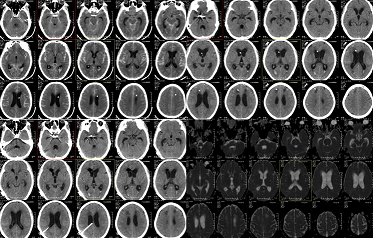

患者,男,60岁,因无明显诱因出现不省人事,躁动不安,无恶心、呕吐,无肢体抽搐,无大小便失禁,发病后被送到当地医院就诊,行头颅CT检查提示:广泛性蛛网膜下腔出血,并在当地医院给予对症治疗,不能控制病情,之后由我院救护车接回。问诊病史发现,患者既往发现高血压病10年,血压最高达180/110mmHg,不规律服药,控制不佳。入院查体:血压160/95mmHg,浅度昏迷,躁动不安,刺痛不能睁眼,四肢肌力4级,双侧瞳孔等大,直径约3.0mm,对光反射迟钝;颈抵抗。

诊断:1、右侧脉络膜动脉瘤破裂出血2.自发性蛛网膜下腔出血3、高血压病3级(极高危组)4.梗阻性脑积水5.双眼玻璃体浑浊并出血

治疗:入院后急诊行脑室外引流+ICP探头置入术,2015.12.23在全麻下行全脑血管造影+动脉瘤介入栓塞治疗(影像显示:右侧脉络膜动脉瘤,囊状,窄颈,大小约4.0mm*3.5mm,朝右后生长,余脑血管造影未见明显异常,确定该右侧脉络膜动脉瘤为责任动脉瘤,行该动脉瘤栓塞治疗)。颅内压高,蛛网膜下腔出血多,尝试夹闭拔管失败,2015.12.30行另一侧脑室外引流术,术后持续引流血性脑脊液,每天引流约200ml血性脑脊液,但夹管后ICP迅速上升至30mmhg以上,多次夹闭引流管,尝试拔除失败,遂于2016.1.12行脑室腹腔分流术,术后腰穿证实压力与引流泵压力一致,引流通畅,经积极治疗,病情逐渐平稳,病情稳定后给予高压氧等康复治疗,经治疗神志逐渐清醒,清醒后感双眼视物模糊,转外院治疗,诊断为双眼玻璃体浑浊并出血,并在该院行双眼玻璃体切除,积血切除术。经跟踪随访病人术后双眼视力改善,视力逐渐恢复。